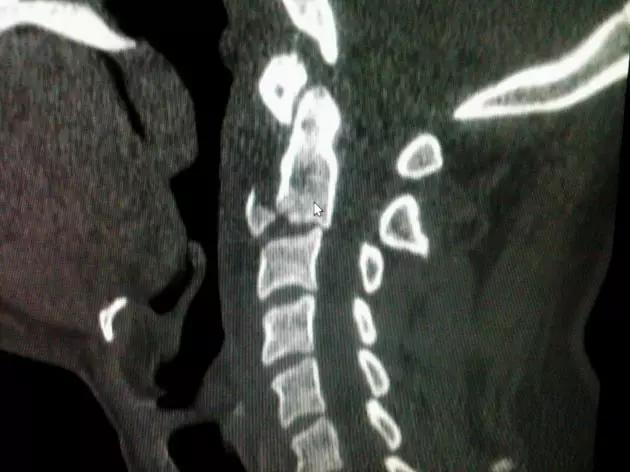

6. Jefferson 骨折

寰椎环的压缩性骨折,骨折是由枢椎压缩性外力引起,骨折多发生在寰椎前侧后侧以及侧方小关节。

第一颈椎双侧性前、后弓骨折,X 线片上很难发现骨折线,有时在正位片上看到 C1 关节突双侧性向外移位,侧位片上看到寰椎前后径增宽及椎前软组织肿胀阴影,CT 检查最为清楚,而 MRI 检查智能显示脊髓损伤情况。

A 图是稳定的 Jefferson 骨折(横韧带完整)轴位像。B 图是不稳定的 Jefferson 骨折(横韧带撕裂)轴位像